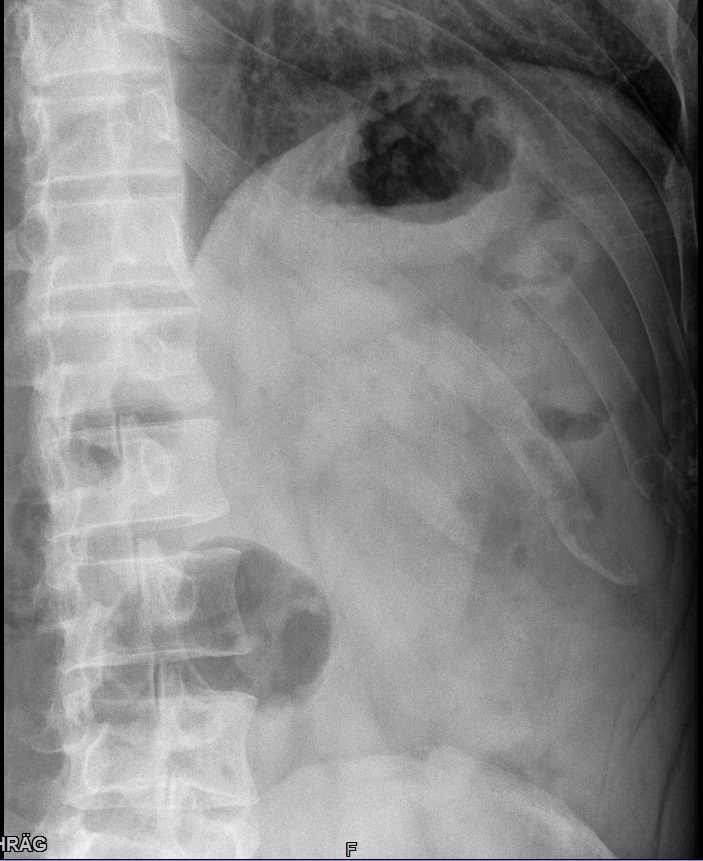

Fehler

Rippen 7-9 werden vom Kassettenrand abgeschnitten. Eine Beurteilung ob die Kortikalis intakt ist, kann hier nicht getroffen werden.